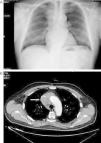

Varón de 71 años hipertenso, dislipémico, con antecedentes de fibrilación auricular, anticoagulado y con cardiopatía isquémica estable. Consultó en el servicio de urgencias por inflamación en cara, cuello y hombros de 15 días de evolución sin síndrome constitucional ni clínica respiratoria previa. En el examen físico presentaba presión arterial de 139/81mmHg, 62 latidos/min y auscultación cardiopulmonar normal. Destacaba el edema en tórax superior, cuello y cara. En la radiología de tórax se objetivó una masa mediastínica superior derecha (fig. 1A), por lo que se realizó una tomografía computarizada (TC) torácica que informó de una masa en mediastino superior derecho que infiltraba y ocluía la VCS (fig. 1B) y pequeñas adenopatías paratraqueales inferiores e hiliar derecha. El hemograma mostró ligera leucocitosis de 10.400/uL. La bioquímica, la coagulación y los marcadores tumorales (alfa-fetoproteína, PSA, CEA, Ca. 19.9 y β2 microglobulina) fueron rigurosamente normales. Se realizó TC abdominopélvica, que descartó alteraciones en otros territorios. Se inició tratamiento con dexametasona, con gran mejoría clínica del paciente, y se procedió a la biopsia guiada por TC, que fue informada como carcinoma tímico. Según el sistema de estadificación de Masaoka se trataba de un estadio III-IVb (invasión microscópica de órganos vecinos [VCS en este caso] y metástasis linfáticas paratraqueales inferiores e hiliar derecha). El paciente fue dado de alta con corticoides y continuó el tratamiento quimioterápico con carboplatino y etopósido. Posteriormente recibió, sin éxito, radioterapia para intentar disminuir la masa tumoral y conseguir la resecabilidad quirúrgica de la misma.